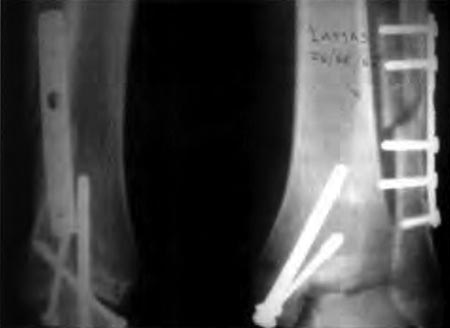

La causa más frecuente de artrosis fue la postraumática (diez casos).(Fig. 1) Otras etiologías fueron Artritis Reumatoidea en dos casos, artropatía hemofílica dos tobillos en un paciente, secuela de poliomielitis un caso, osteocondrítis de astrágalo un caso.

Figura 1 a: Rx de tobillo con osteosíntesis

Figura 1 b: artrosis secundaria 2 años después